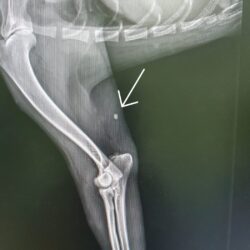

Blanca allerdings wurde total abgemagert und schwach aufgelesen. Da sie nicht einmal gehen konnte, wurde ein Röntgen gemacht um zu schauen, ob etwas gebrochen war. – Sie war aber einfach nur total unterernährt.

Das Röntgenbild zeigte jedoch eine Schrotkugel im Bein, die Blanca aber in keiner Weise stört.(s.Photo)